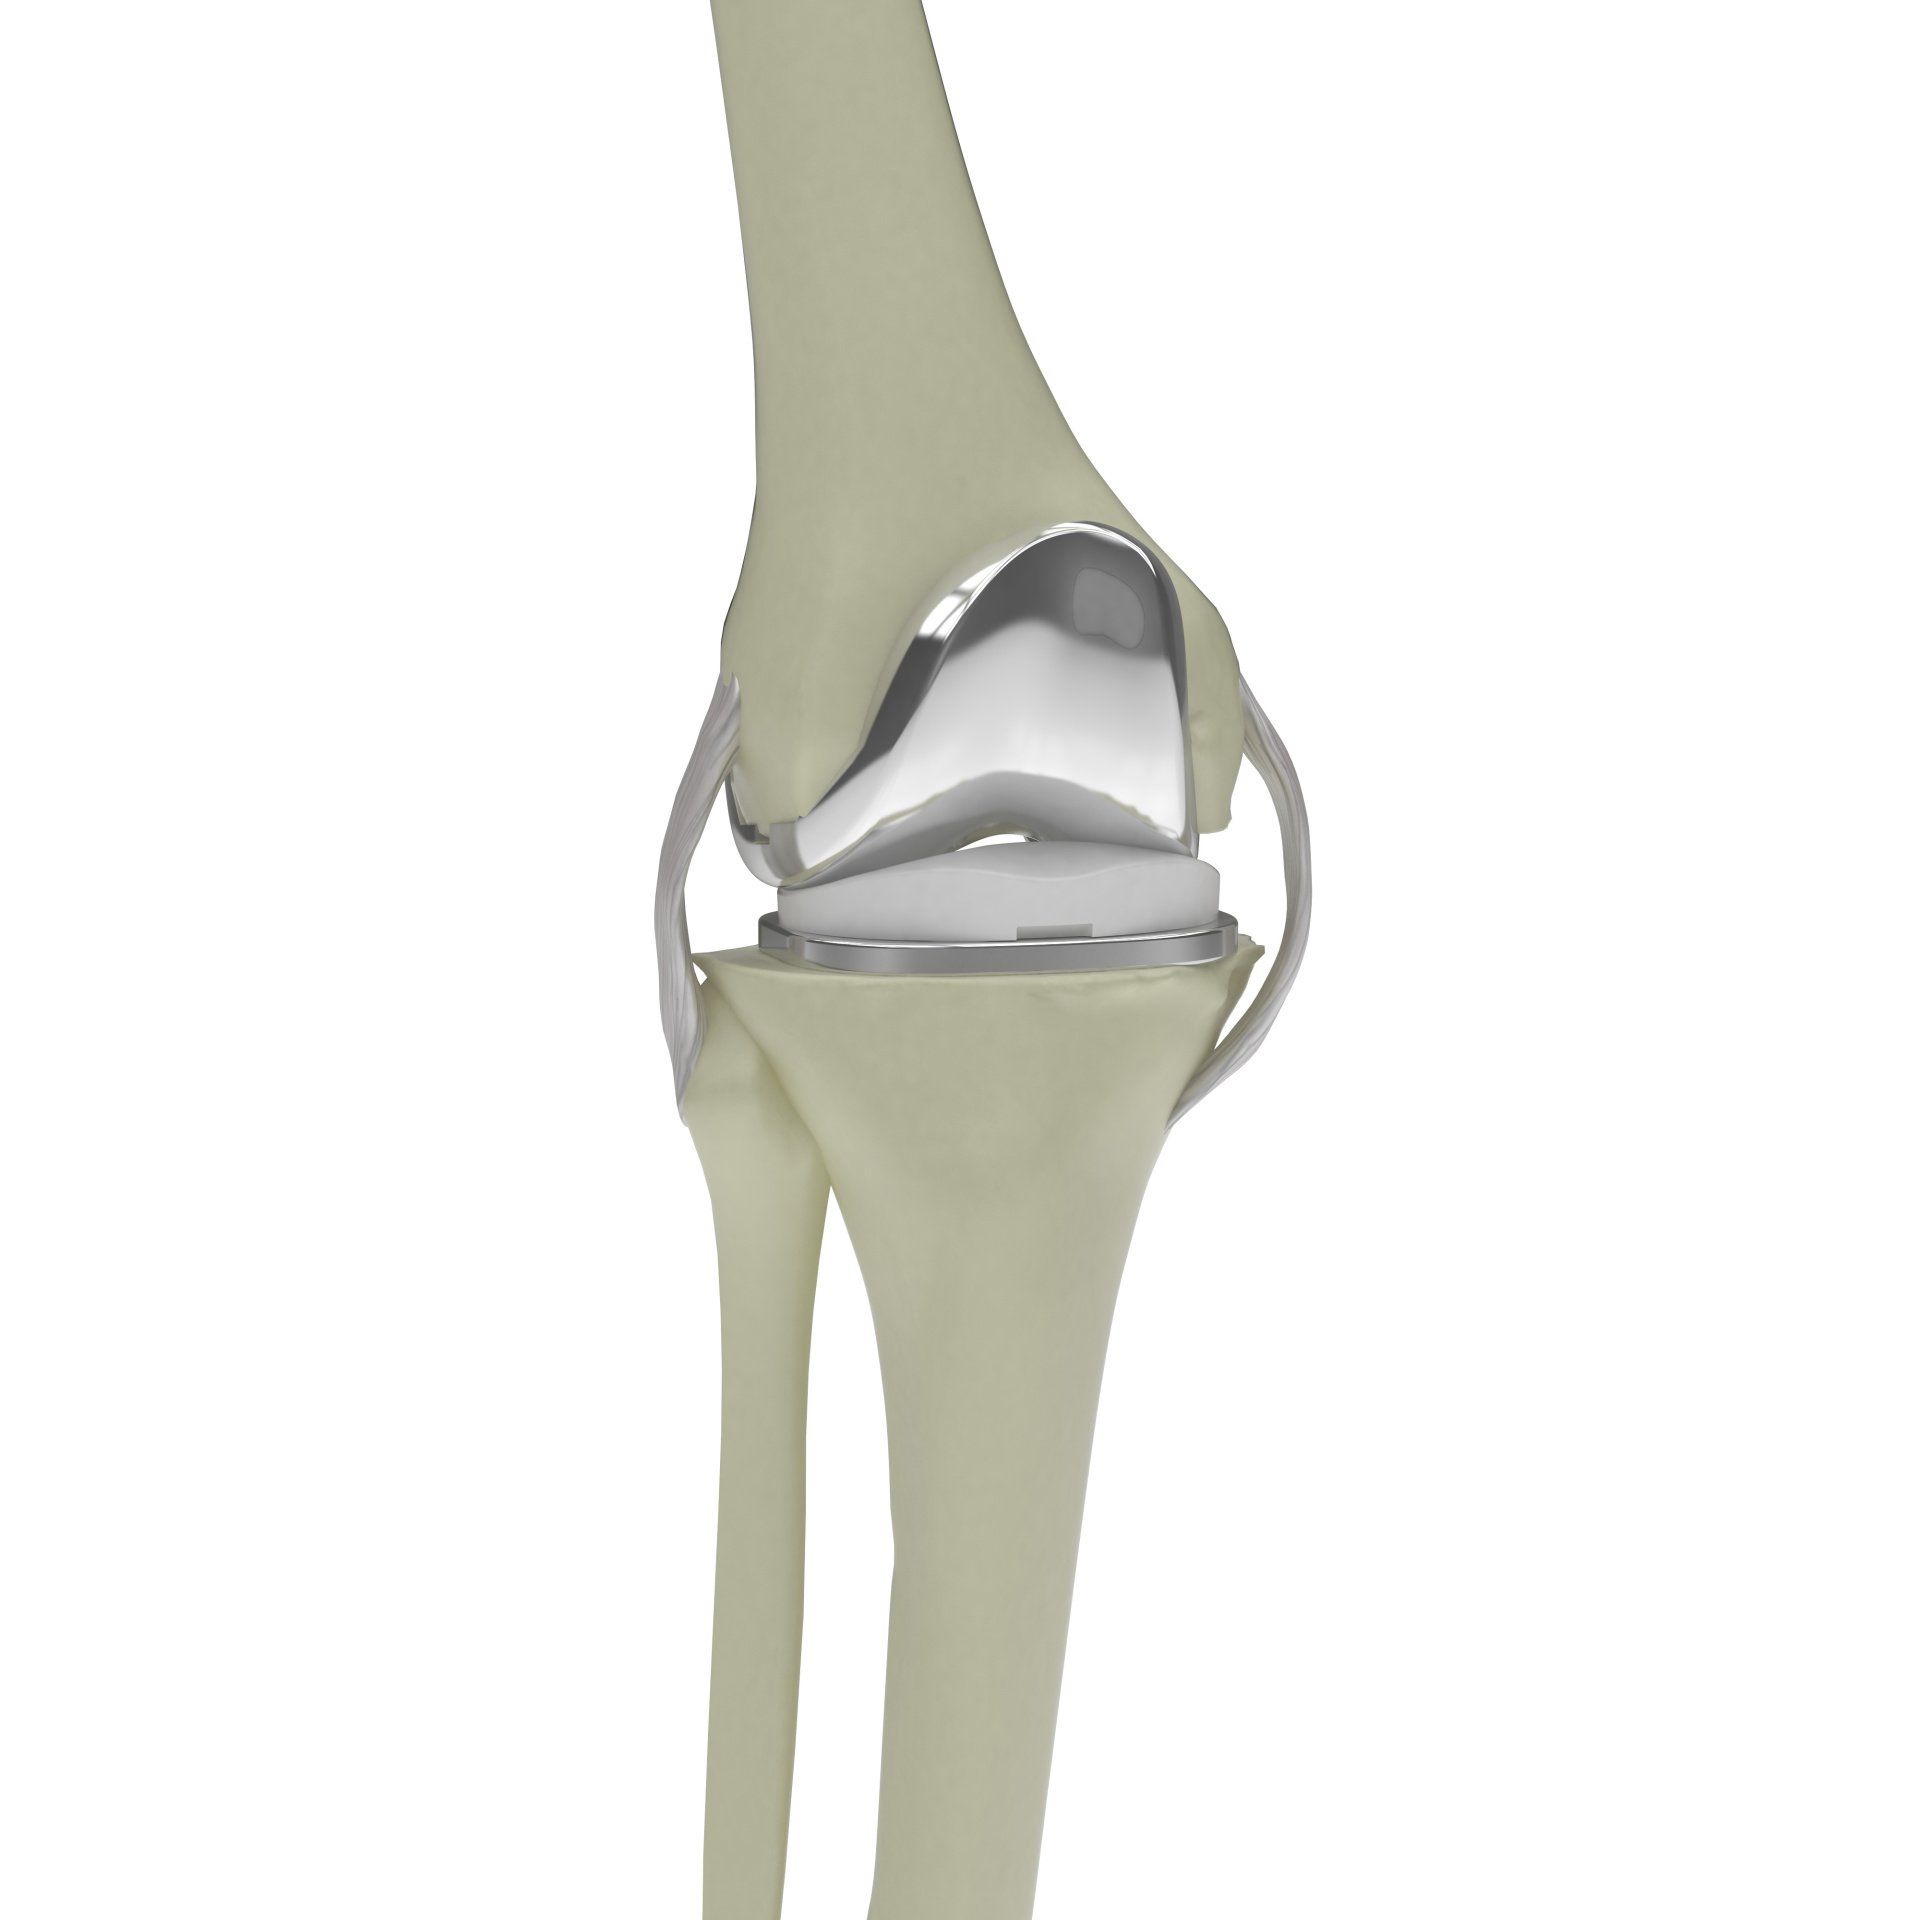

- Η ολική αντικατάσταση του γόνατος (αρθροπλαστική) περιλαμβάνει την αφαίρεση λεπτού στρώματος της αρθριτικής (φθαρμένης) αρθρικής επιφάνειας του μηριαίου και της κνήμης και την αντικατάστασή του με μέταλλο το οποίο καθηλώνεται στη θέση του με ειδικό οστικό τσιμέντο

- Μεταξύ των δύο μεταλλικών επιφανειών τοποθετείται ένα πλαστικό ένθετο (πολυαιθυλένιο) έτσι ώστε να γλιστράνε εύκολα οι μεταλλικές επιφάνειες μεταξύ του μοιραίου οστού και της κνήμης

- Σε επιλεγμένες περιπτώσεις (που εξαρτάται από το βαθμό φθοράς και τον πόνο στο πρόσθιο τμήμα του γόνατος), η οπίσθια επιφάνεια της επιγονατίδας μπορεί επίσης να αντικατασταθεί με πολυαιθυλένιο το οποίο στερεώνεται στη θέση αυτή με τσιμέντο